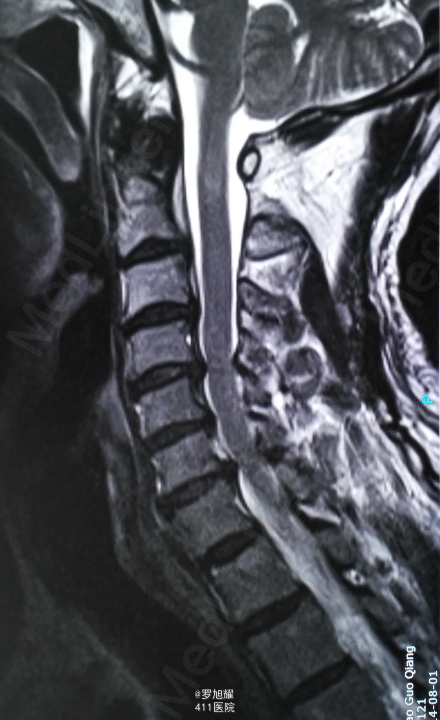

左侧锁骨平面以下痛温觉、位置觉消失,右半身感觉正常。会阴部感觉存在。左侧肢体肌力正常,右侧上下肢肌力0级。右侧腱反射均消失。影像学检查示双侧枢椎椎弓骨折,MRI脂肪抑制成像颈1-2平面脊髓信号略高。

入院立即给与大剂量甲强龙冲击治疗,辅以甘露醇脱水消肿,兰索拉唑保护胃黏膜,腺苷钴胺恩经复营养神经,伤后10天复查MRI脊髓信号增高明显,两周后生命体征稳定,肢体感觉和肌力见部分恢复,行颈2椎弓根螺钉、颈3侧块钉内固定术,因神经压迫不明显未行椎板切除减压。 术后3月骨折线基本消失,患者感觉肌力几乎完全正常,右肩残留疼痛磁共振检查发现肩袖损伤,暂予局封治疗症状缓解。